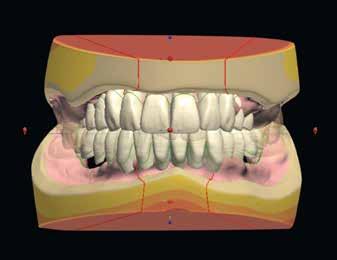

Dr. Miguel Stanley, dr. Ana Gomes Paz, dr. Inês Miguel (Portugália) Dr. Christian Coachman (Brazília) 1. ábra: Kiindulási állapot (frontális irányból). 2. ábra: A kiindulási állapotról okkluzális irányból készített felvétel (felső állcsont). 3. ábra: A kiindulási állapotról okkluzális irányból készített felvétel (alsó állcsont). 4. ábra: A kiindulási állapotról készült panorámaröntgen felvétel (2015).

2015-ben egy 47 éves férfi páciens állkapocs-ízületi panaszai miatt kereste fel a rendelőnket. Ezen felül esztétikai problémát jelentett számára, hogy az egyik felső nagymetszőfogán lévő héj eltört (1-3. ábrák). A klinikai és radiológiai vizsgálatot követően megállapítható volt, hogy a páciens kifejezett bruxizmusa miatt csökkent a harapási magassága, és jelentős mennyiségű saját foganyagot abradált el (4. ábra)

tük. Az új harapási magasságot a CAD/CAM szoftverben létrehozott virtuális artikulátor általunk meghatározott mértékig történő nyitásával határoztuk meg.

A már előzetesen preparált felső frontfogak csiszolt csonkjainak megtartottuk az eredeti formáját. Az alsó és felső őrlőfogak preparációja nem volt szükséges (1.7-1.4, 2.4-2.7, 3.7-3.4, 4.4-4.7), az alsó kismetsző fogakat minimál invazív módon készítettük elő. Az előkészítést követően új digitális lenyomat készült. Az így kapott digitális adatokat továbbítottuk a fogtechnikai laboratóriumba (9. ábra). A virtuális modellt ezek alapján hozták létre (AnatomicLab), és a minta elkészítéséhez szükséges STL fájlt továbbították egy háromdimenziós nyomtatóra (SolFlex 650, VOCO), amely segítségével elkészítették az új mintát (V-Print model, VOCO).

A végső restaurátumokat (héjakat és koronákat) Ce-

ramill Mind tervező program segítségével (AmannGirrbach) digitálisan megtervezték, majd frézgép segítségével (CeramillMotion 2, AmannGirrbach) li thium-diszilikát tömbökből (VITABLOCS TriLuxe forte for CeramillMotion 2, AmannGirrbach) kifaragták (10. ábra). Miután a fogpróba során ellenőrizték és megfelelőnek találták a pótlások széli záródásának a pontosságát, valamint az elkészült restaurátumok esztétikai megjelenését, ezután egy ajak- és szájterpesz került felhelyezésre (OptraGate, IvoclarVivadent).